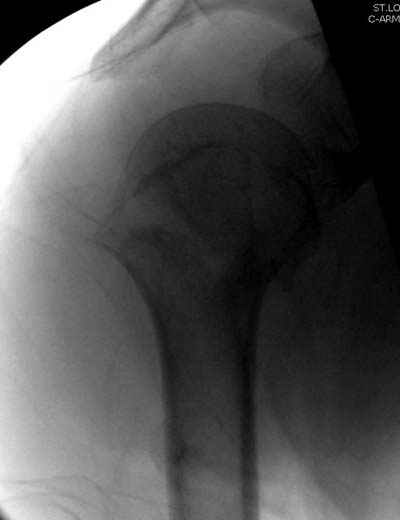

Клинические снимки - 3 недели после операции

с уважением М. Беренштейн

Посылаю послеоперационные Рг граммы.

Всего Доброго,

Поздравляю, получилось просто замечательно. Если можно, расскажи чуть подробнее, как делали - как вправляли, как вводили спицы, поворачивали ли их?